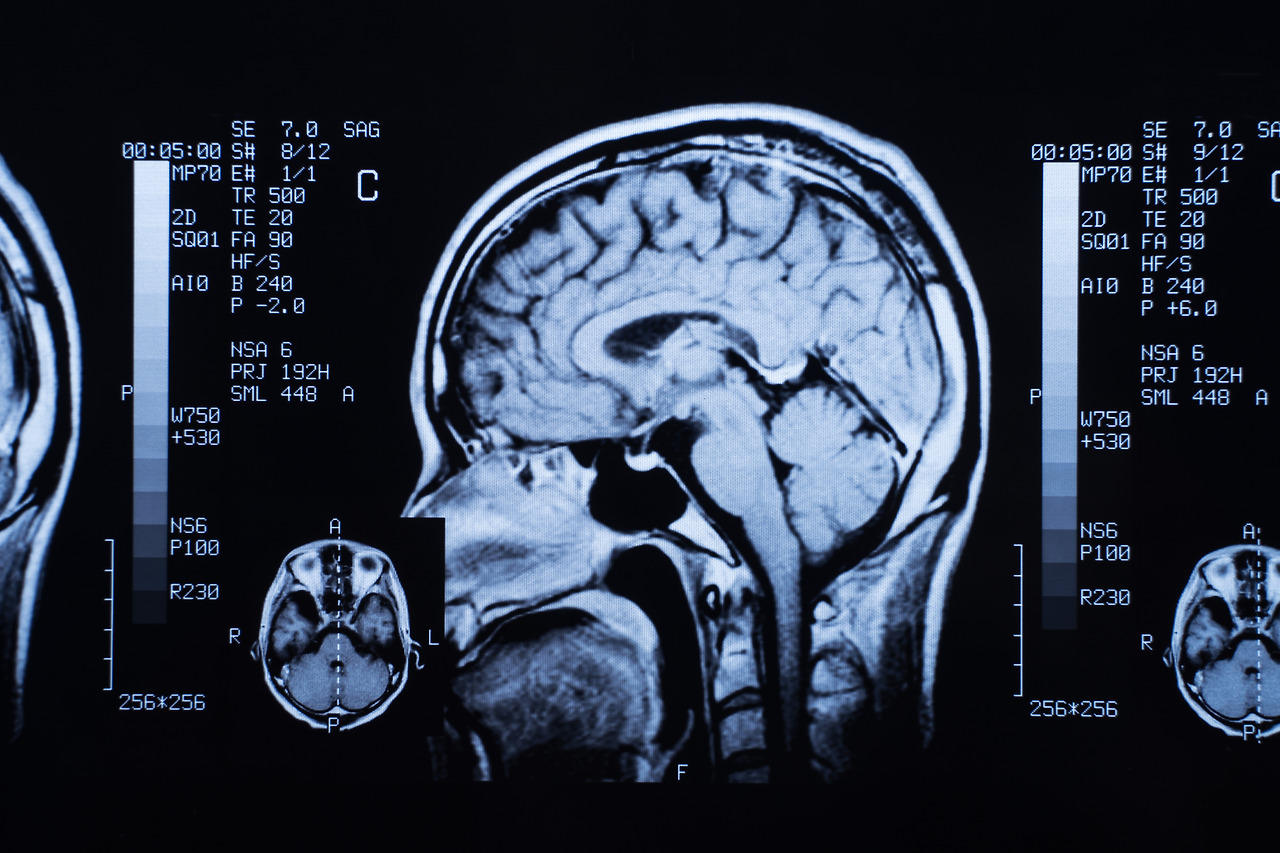

뇌 MRI 검사는 뇌혈관질환, 뇌종양, 뇌출혈, 신경학적 이상 증상 등을 평가할 때 필수적으로 활용되는 정밀 진단 장비이며, 강한 자기장을 이용해 인체 내부를 고해상도로 촬영하는 방식입니다. 최근 두통, 어지럼, 이상감각, 시야 흐림 등 다양한 증상에서 MRI 검사가 권고되는 사례가 증가하면서 많은 분들이 검사 비용, 촬영 시간, 조영제 여부에 따른 금식 필요성 등을 궁금해합니다.

뇌 MRI 검사는 크게 비용 구조와 촬영 절차, 금식 조건으로 나누어 이해할 수 있습니다. 비용은 건강보험 적용 여부가 가장 큰 변수이며, 시간은 MRI 장비 성능과 촬영 부위, 조영제 사용 여부에 따라 달라집니다. 금식은 기본적으로 필요 없지만 조영제 촬영에서는 일정 시간 금식이 요구된다는 특성이 있습니다.